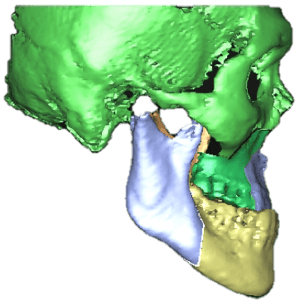

Surgical correction of the underbite is relatively more invasive than dental implant surgery. It requires a general anesthetic and staying in the hospital for a day or two. The postoperative downtime is also longer and the potential for complication such as nerve injury is also higher. However, it offers a chance for the patient to have a more aesthetic facial appearance and the placement of implants in positions that enable the dental prosthesis to achieve optimal function and aesthetics. I will usually do an orthognathic surgical plan complete with simulation of post-operative facial changes to illustrate the effect of such a plan. As with conventional orthognathic surgery, perioperative orthodontic treatment is needed and that is yet another consideration that a patient will need to undertake as orthodontic treatment typically will take one to two years to complete.

There were three options. We can start off with orthodontic decompensation to align the teeth within each jaw. Thereafter, the lower jaw can be surgically repositioned backwards to eliminate the underbite. This is then followed by dental implants to replace the missing teeth. However, the patient was not keen on orthognathic surgery.

A compromise plan was eventually undertaken. Orthodontic treatment was done to open the bite, align the teeth and tilt the upper front teeth out and lower front teeth back to achieve a positive overbite and overjet. By raising the bite, more space is created for placement of implant supported crowns. This increase in vertical dimension also created better facial proportions. Originally, with the lower jaw postured forward, the bite was over-closed, shortening the height of the lower third of the face. Opening up the bite increases the vertical dimension of the lower third giving a more natural proportion. (Due to regulations in Singapore, after photos cannot be included.)